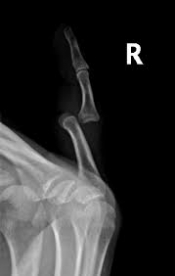

Letsel van de vinger Gepost op 18 juni 201718 juni 2017 door netwerkvsseh Finger injuries @ emdaily.cooperhealth.org Dit delen: Delen op X (Opent in een nieuw venster) X Share op Facebook (Opent in een nieuw venster) Facebook Delen op LinkedIn (Opent in een nieuw venster) LinkedIn E-mail een link naar een vriend (Opent in een nieuw venster) E-mail Afdrukken (Opent in een nieuw venster) Print Vind-ik-leuk Aan het laden... Gerelateerd